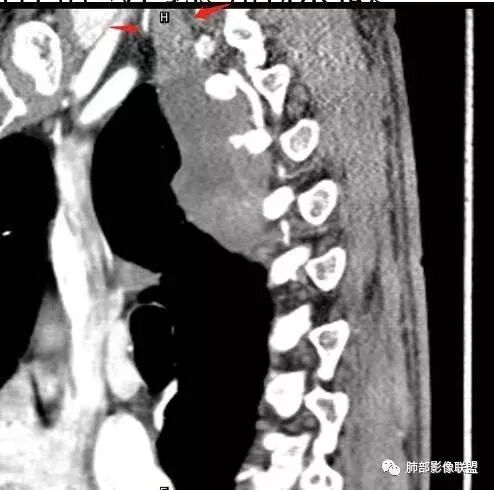

南边: 这是病灶吗

南边: 上面可能与锁骨伪影干扰有关

病灶内的肋间动脉穿行代表什么?

答:代表病灶内供血血管或病灶具有侵袭性将血管包绕其中。提示病灶的肺外来源属性。